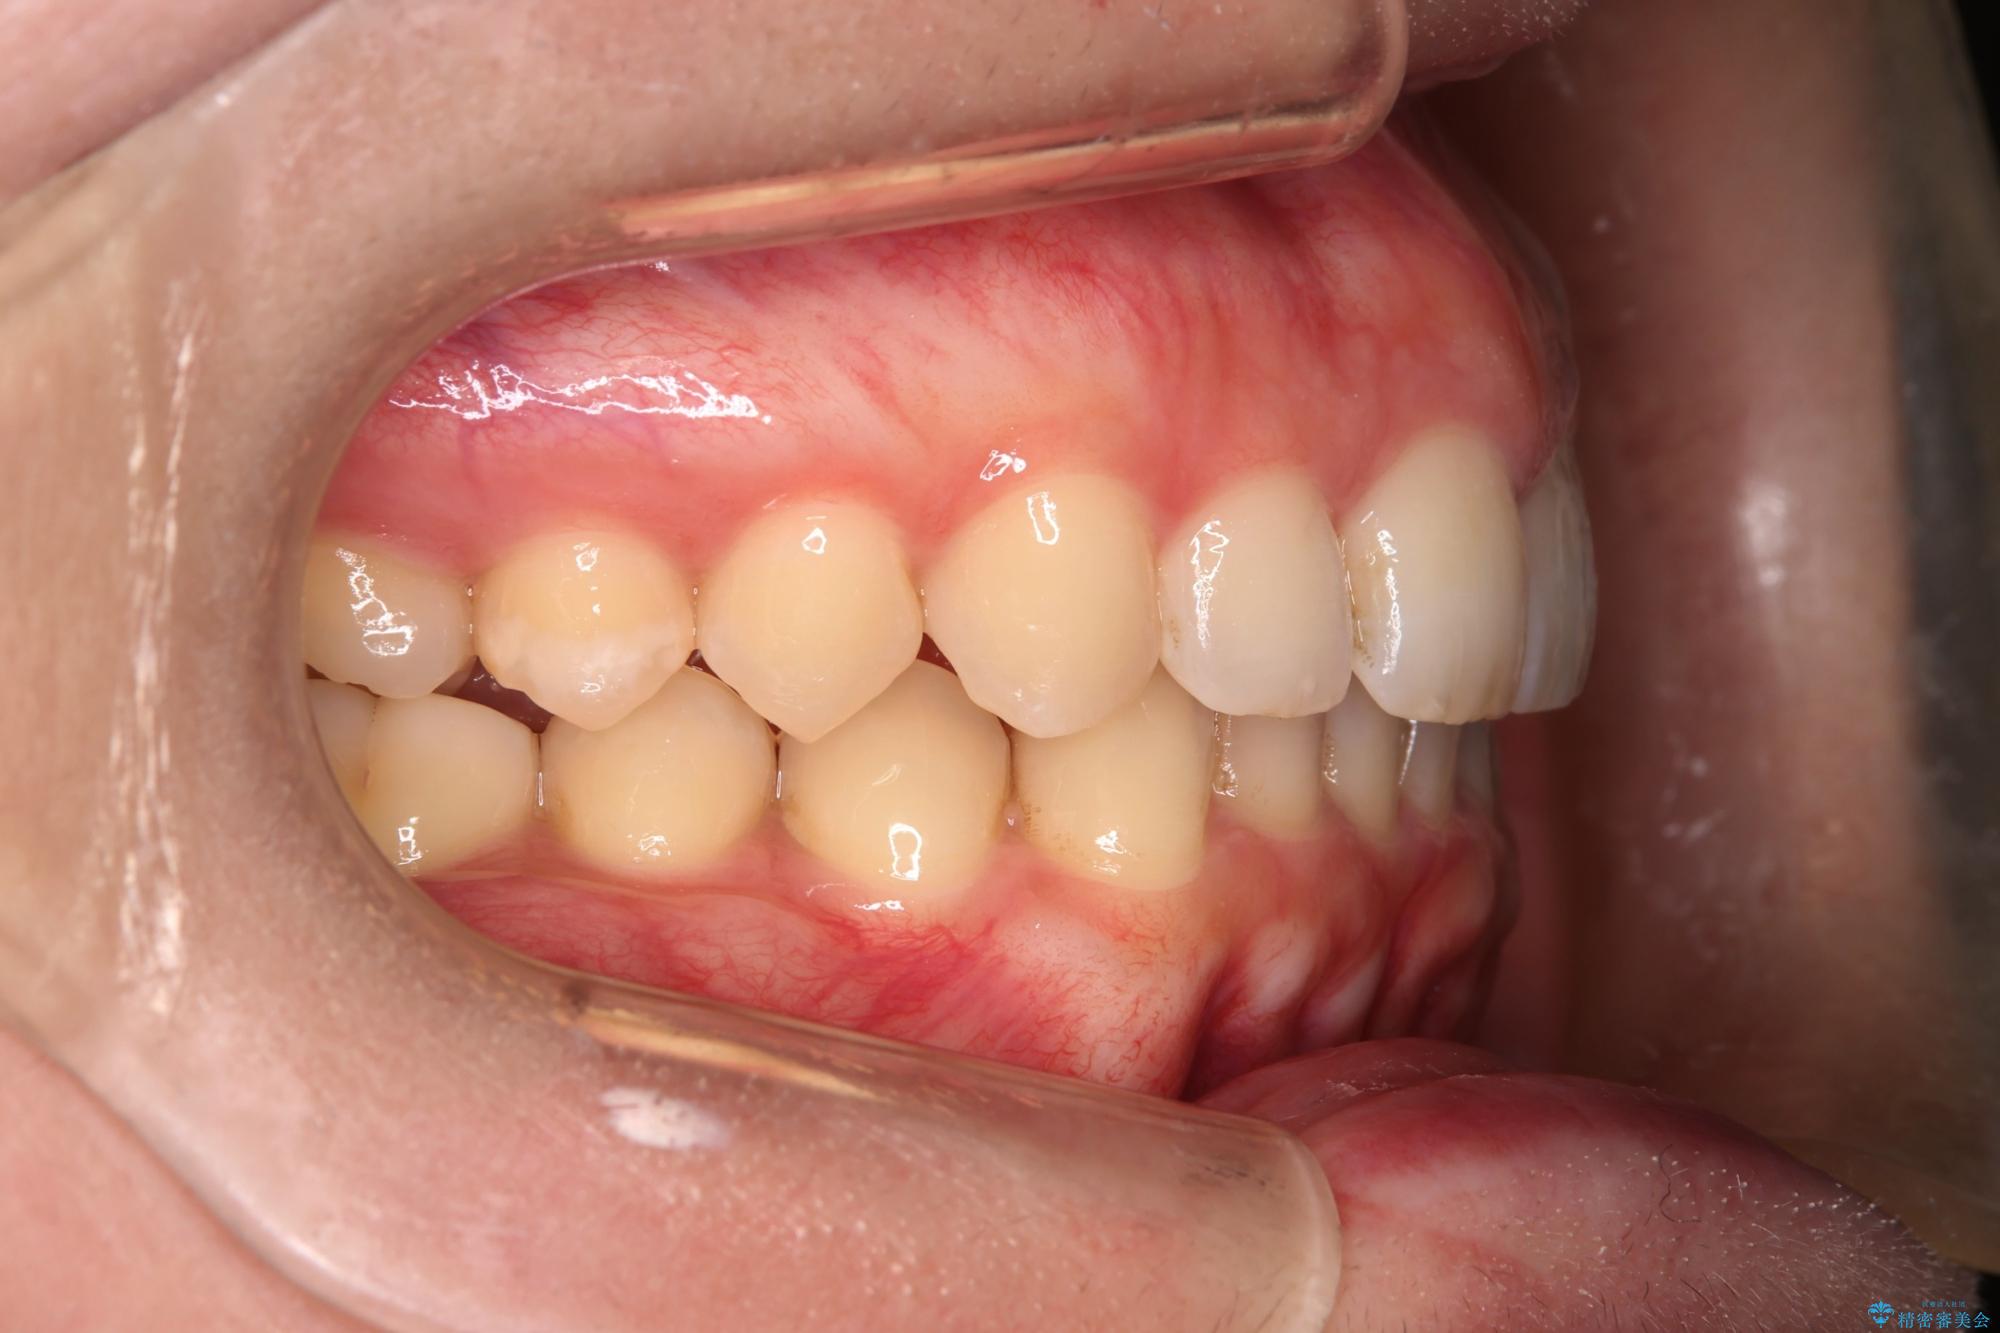

噛み合わせをよくするために、ワイヤー矯正とインビザライン矯正のどちらの期間も必要な箇所にゴム掛けを行いながら治療を行いました。

下の前歯のがたつき改善にはIPR(歯と歯の間を削る処置)を行いました。

ゴム掛けを頑張っていただいたので、噛みあわせも改善され綺麗な歯並びになりました。